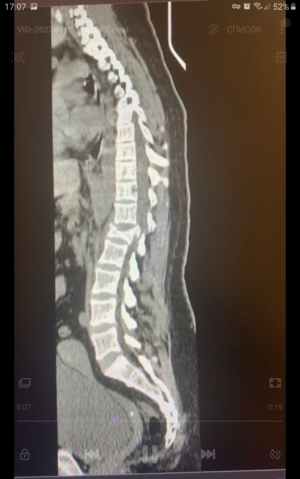

Новый клинический случай у травматологов КМКБСМП. Молодая женщина была доставлена в больницу с травмой позвоночника, которую получила во время спуска с горы на тюбинге.

Из практики врачей-травматологов травмы на тюбинге случаются, как правило по одному сценарию. Пострадавшие для популярного зимнего развлечения выезжают за город и выбирают необорудованные для спуска склоны, в результате столкновения, отдыхающие получают серьезные травмы. В последнем случае, женщина на скорости выпала из «плюшки», в результате был серьезно травмирован позвоночник.

Оперативное лечение для пострадавшей проходило в несколько этапов. Травматологами была проведена транспедикулярная фиксация позвоночника системой позвоночных винтов, то есть в месте травмы позвонки были зафиксированы при помощи специальных имплантов.